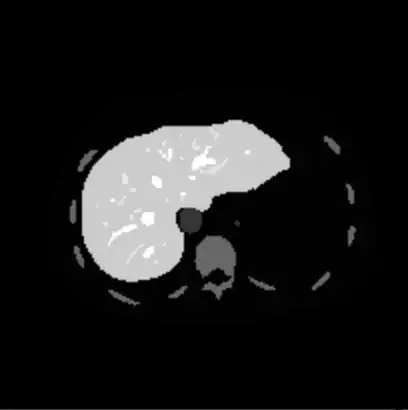

The image below contains the tumour.

This image is the actual DICOM image